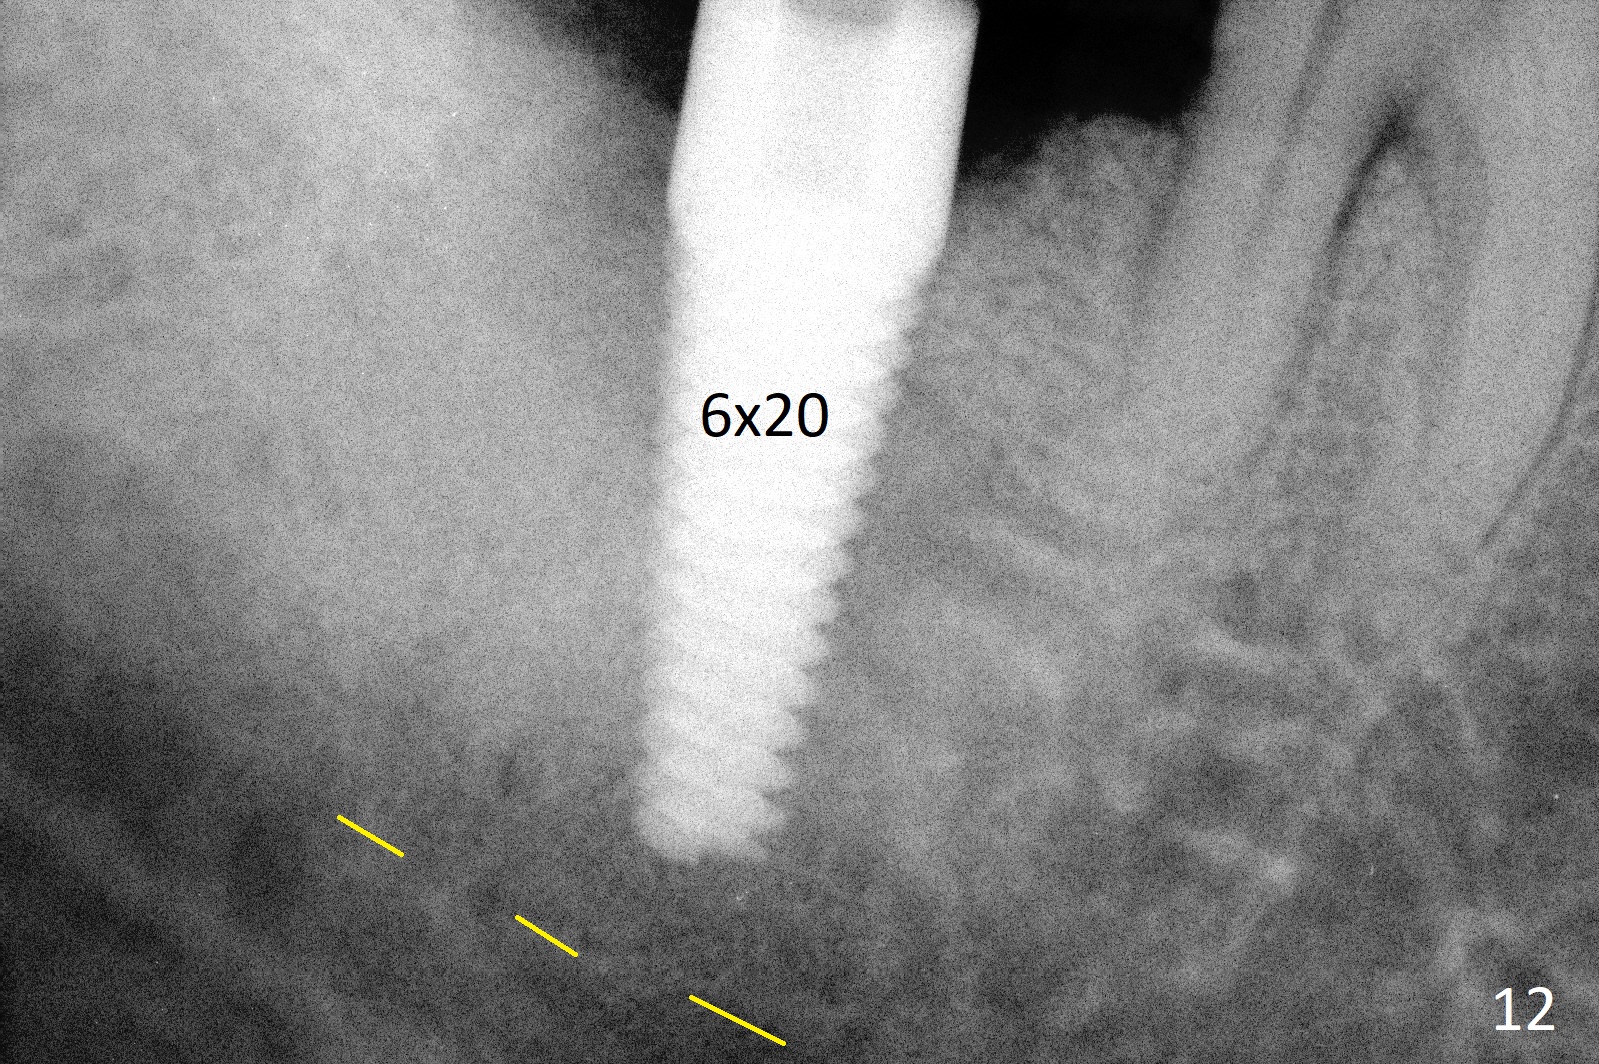

A 50-year-old man, a smoker, presents to clinic with pain of the tooth #15 with apparently occlusal trauma (Fig.1). Two years and three months after #15 extraction, he returns for #31 extraction (Fig.2) and socket preservation (Fig.3). The socket depth is 17 mm along the long axis of the socket 2.5 months post extraction (Fig.4, gingival level). Initial osteotomy is created in the mesial slope of the socket for 14 mm (Fig.5). After sequential osteotomy, a 6x17 mm tap is seated shallower (Fig.6) than the 2 mm drill (Fig.5). Following further osteotomy, a 7x14 mm implant is seated incompletely (Fig.7), which was not found intraop. The implant becomes loose with purulent discharge 19 days postop. The patient returns for 2nd placement 2 months post implant removal (Fig.8). Osteotomy is created probably in the mesial slope with 17 mm (bone level, Fig.9). After insertion of 5 (Fig.10) and 6 (Fig.11) x20 mm taps (tissue level), a 6x20 mm tissue-level implant is placed with clearance from the Inferior Alveolar Canal (Fig.12 yellow dashed line). The implant is restored 8.5 months postop (Fig.13) without bonding 5 mm 0 degree unipost. The crown dislodges 4 months post permanent cementation. Still the patient complains of small crown without occlusal contact. Impression is taken for a new normal-sized crown. The new crown becomes loose 1 year 9 months post cementation (Fig.14). The teeth #14 and 15 remain unrestored.